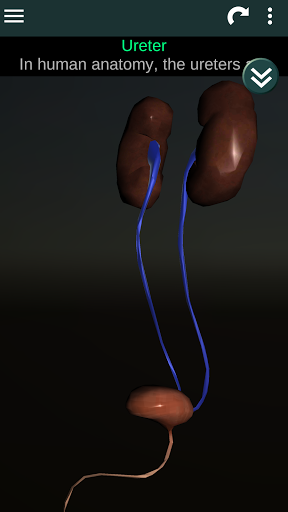

(الأجهزة الداخلية في)

Internal Organs 3D Anatomy 3.4

يمكنك هنا تنزيل ملف حزمة تطبيق أندرويد "Internal Organs 3D Anatomy" الخاصة بجهازVodafone Smart N9 Lite مجانًا، نسخة ملف حزمة تطبيق أندرويد - 3.4 للتحميل على Vodafone Smart N9 Lite اضغط ببساطة على هذا الزر. إنه سهل وآمن. نحن نقدم فقط ملفات حزمة تطبيق أندرويد الأصلية. إذا انتهكت أية مواد موجودة في الموقع حقوقك قم بإبلاغنا من خلال